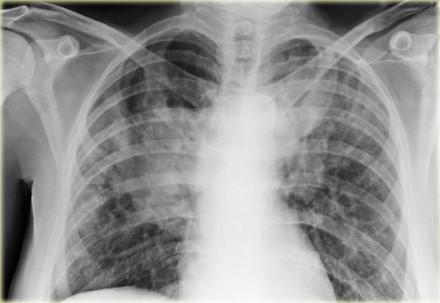

Interstitial lung disease (ILD) rarely occurs in patients with systemic lupus erythematosus (SLE), but when it does, ILD is often associated with other systemic autoimmune disorders and may even significantly contribute to mortality, according to a study.

“Besides pleuritis—the most common thoracic manifestation of SLE—specific pulmonary manifestations mainly include acute pneumonitis, alveolar haemorrhage, organizing pneumonia, chronic ILD, shrinking lung syndrome, bronchiolitis obliterans, and pulmonary hypertension,” they added. [Thorax 2000;55:159-166; Arthritis Res Ther 2018;20:1-10]